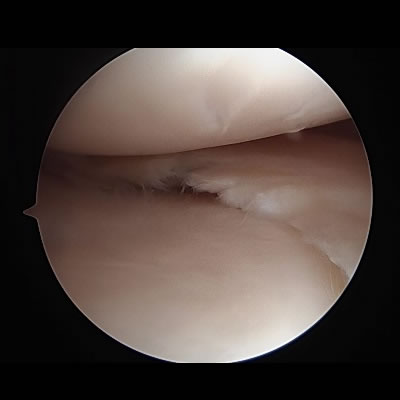

半月板縫合術・半月板切除術(半月板損傷)

関節鏡を用いて、縫合あるいは損傷部位の部分切除を行います。

半月板は膝関節の重要な役割を担っているため、可能な限り縫合を行っておりますが、縫合が困難な場合は切除部位を最小限にとどめられるように行います。